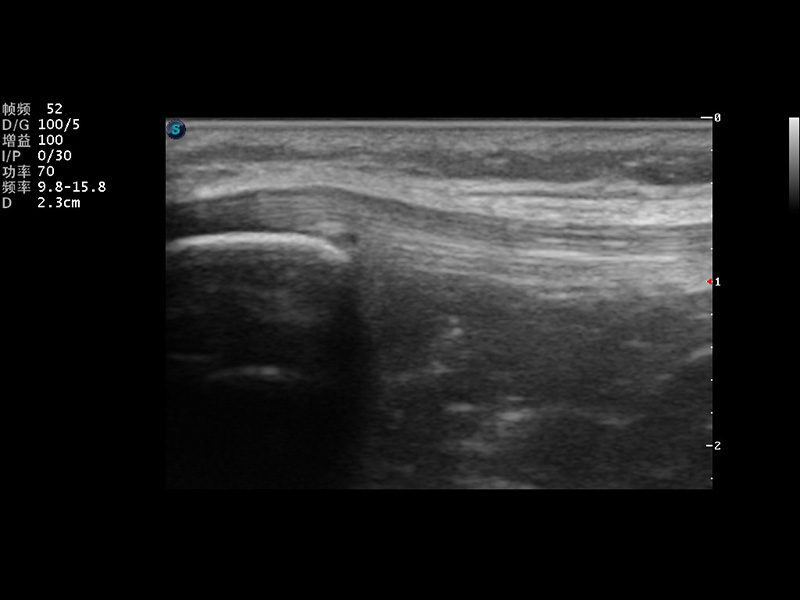

S9便携式彩色多普勒超声诊断仪是新葡的京集团8814检测站研发的高端便携彩超设备,外观设计新颖、产品性能卓越。S9在便携超声领域采用了突破传统的触摸屏交互设计,并以先进的软件硬件技术和设计理念,为您带来清晰的图像质量、稳定的工作性能和便捷的操作体验。

μ-Scan微米成像